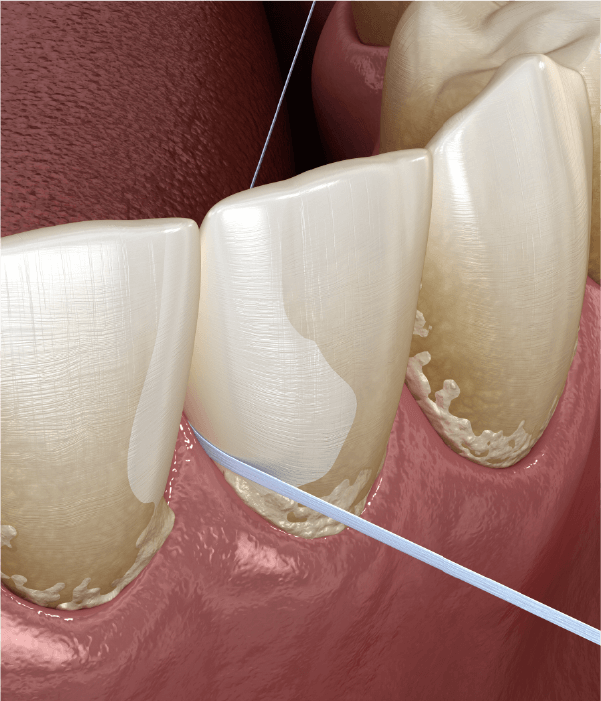

歯石がたまり、細菌が歯肉に繁殖し歯茎を悪化していく恐ろしい病気です。全身疾患と関連が深く、定期的な口腔ケアが必要です。当院では専門的な歯周病治療を行い、全身疾患から守ります。

口腔清掃:歯石を除去する

歯周病治療:歯周組織をキレイにする